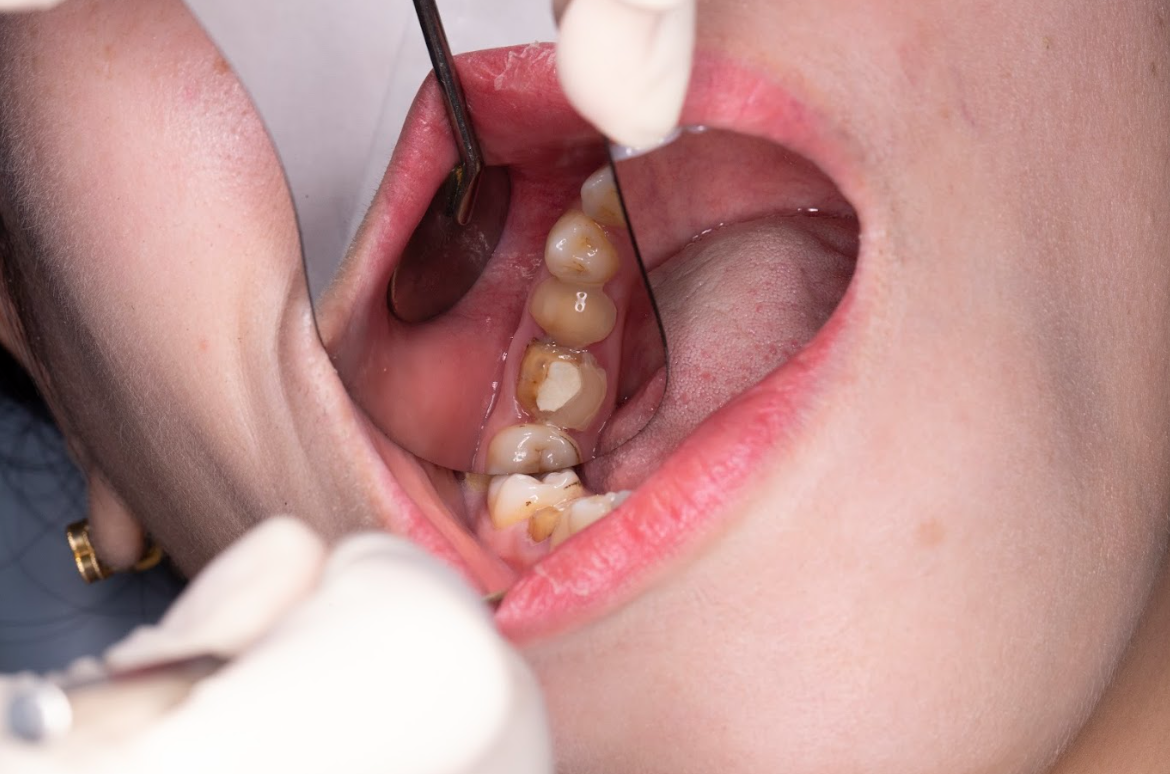

Chị Vân được BS Bùi Văn Hưng trực tiếp thăm khám và thực hiện các bước kiểm tra:

Chụp CT Conebeam 3D để đánh giá tình trạng xương hàm.

Kiểm tra răng trụ đã mài làm cầu → phát hiện có dấu hiệu sâu ngầm và viêm lợi nhẹ.

Đánh giá mật độ xương tại vị trí răng mất → đủ điều kiện cấy Implant, không cần ghép xương.